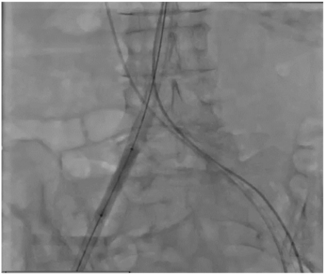

A 54-year-old man suffered a self-inflicted penetrating chest wound from an automated crossbow used for hunting large animals, with an entrance wound in the left third intercostal space and an exit wound at the tenth intercostal space.